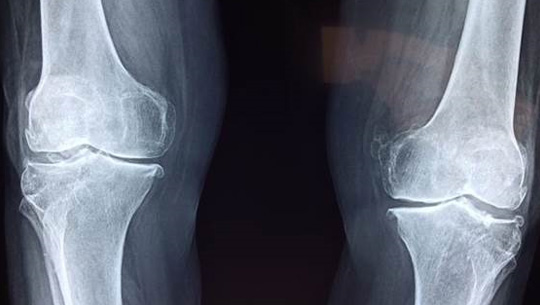

Foto: Pixabay